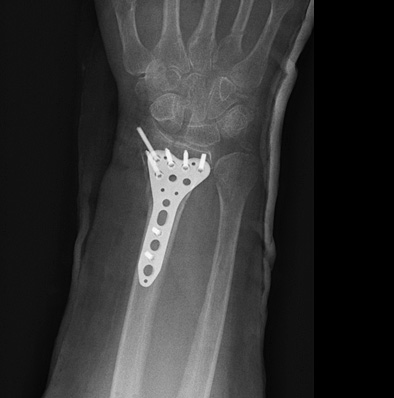

Пациентка М. 70 лет. Упала в быту на улице. При поступлении в клинику диагностированы многооскольчатые переломы дистальных метаэпифизов локтевой и лучевой кости. После закрытой репозиции сохраняется смещение отломков.

На 3 сутки выполнена открытая репозиция и фиксация переломов пластинами и винтами. Положение отломков удовлетворительное, пациентка выписана на амбулаторное лечение.